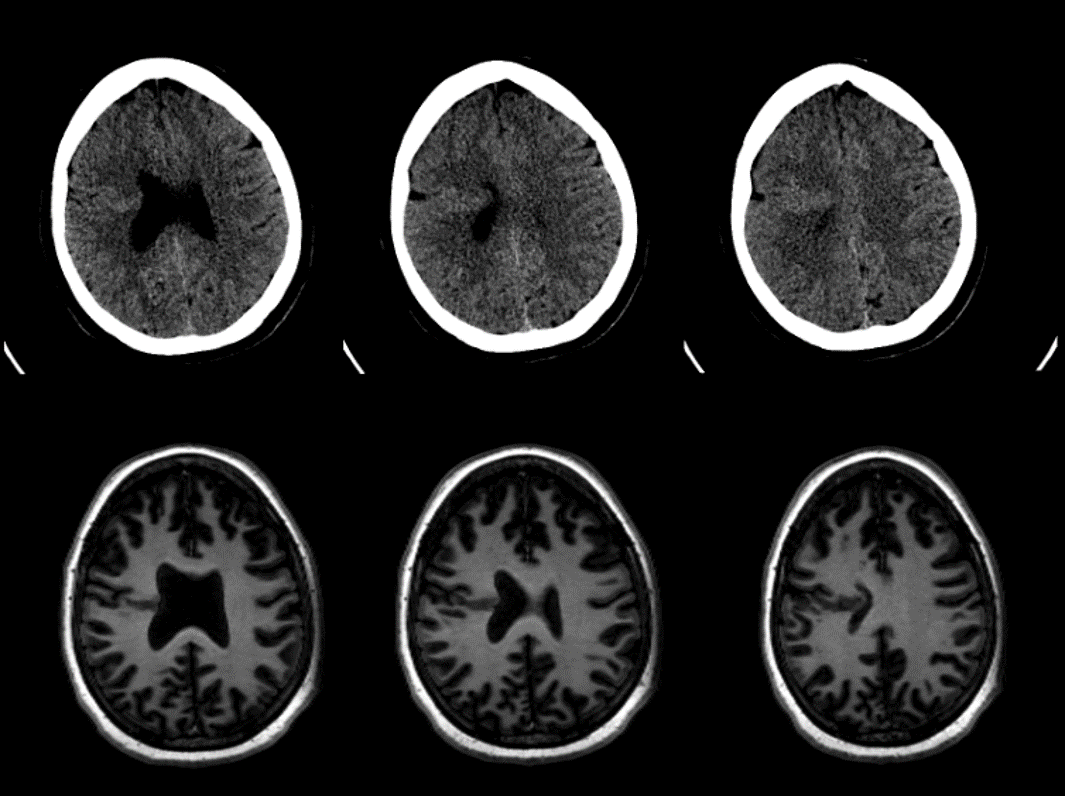

Fila superior: cortes axiales de TC de cráneo simple y Fila inferior cortes axiales de RM de cráneo en secuencia T1.

Se observa un tejido cerebral isodenso/isointenso a la sustancia gris cortical que se introduce hacia la sustancia blanca profunda del lóbulo frontal derecho, extendiéndose desde la superficie del cerebro al ventrículo lateral derecho, en el que se aprecia una pequeña muesca.

También se observa un surco dilatado en la convexidad frontal derecha que se continúa con una pequeña hendidura de densidad/intensidad similar al LCR.

Por último, se identifica una asimetría en los surcos y circunvoluciones de ambos hemisferios, así como una disgenesia del cuerpo calloso.